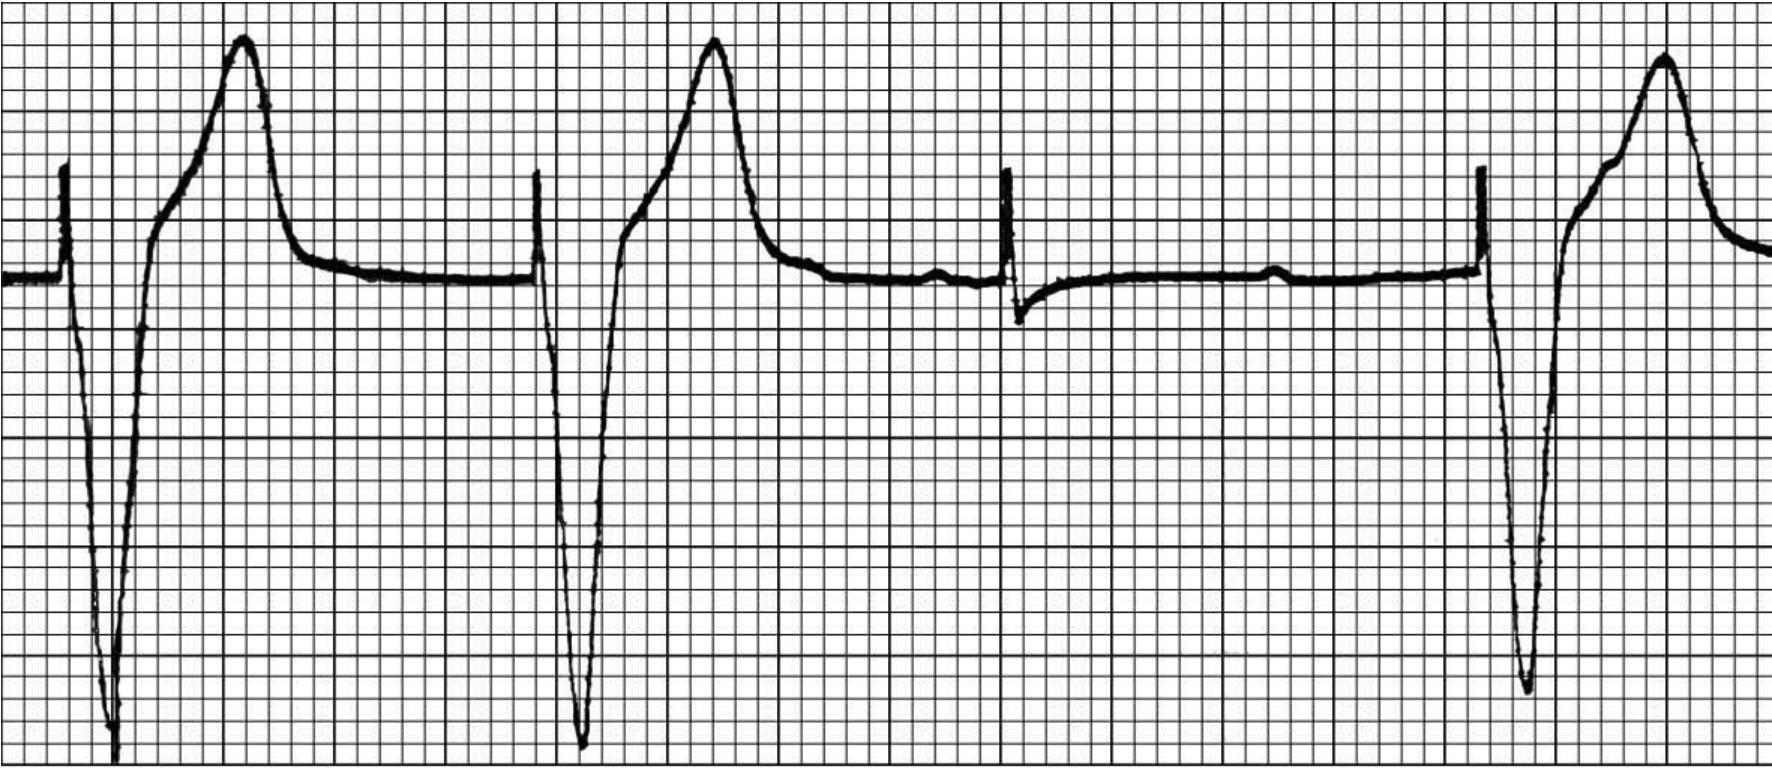

(一)起搏回路及起搏信号 起搏器系统的脉冲发生器输出起搏脉冲,经电极导线刺激和起搏心脏。起搏时,电流由起搏电极(阴极)流向无关电极(阳极)。起搏可以是单极或双极两种形式起搏,并以不同方式组成起搏回路。刺激信号又称脉冲信号或起搏信号,代表脉冲发生器发放的有一定能量的刺激脉冲,脉冲宽度0.2~0.5ms,在心电图上表现为一个直上直下的钉样标记(图61-4)。脉冲信号的幅度与两个电极问的距离成正比关系,双极起搏时,正负两极间距离小,刺激信号较低,在某些导联心电图上几乎看不到脉冲。单极起搏时起搏的正负两极之间的距离大,刺激信号较大,有时还呈双相。刺激信号的另一特点是不同导联记录的刺激信号幅度的高低有一定的差异,这与起搏电脉冲的方向在心电图导联轴上的投影不同有关。有的心电图机描记出来的起搏心电图脉冲信号在同一导联上有正有负,振幅大小差别很大,原因是心电图机的采样率较低,丢失了一部分心电和脉冲信息。

图61-4

刺激信号是起搏器发放的电刺激在心电图上的具体反应,表现为一占时极短、振幅差异较大的电位偏转波